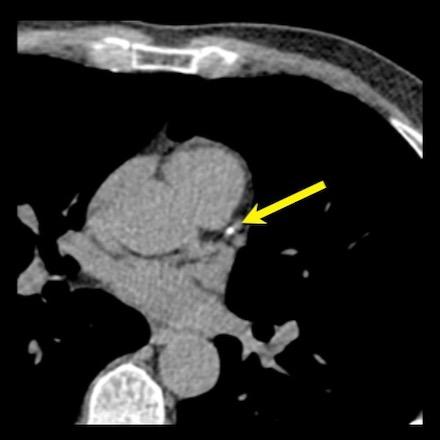

Positive remodeling

Positive remodeling is defined as a compensatory outward enlargement of the vessel wall at the site of the atherosclerotic lesion with preservation of the coronary lumen (8).

On histology plaques with positive remodeling show a higher lipid content and abundance of macrophages (9).

Patients with positive remodeled plaques can present with an acute coronary syndrome without any prior cardiac history.

An example of positive remodeling of a non-calcified plaque in the mid RCA.

There is outward growth of the plaque with minimal stenosis of the lumen.